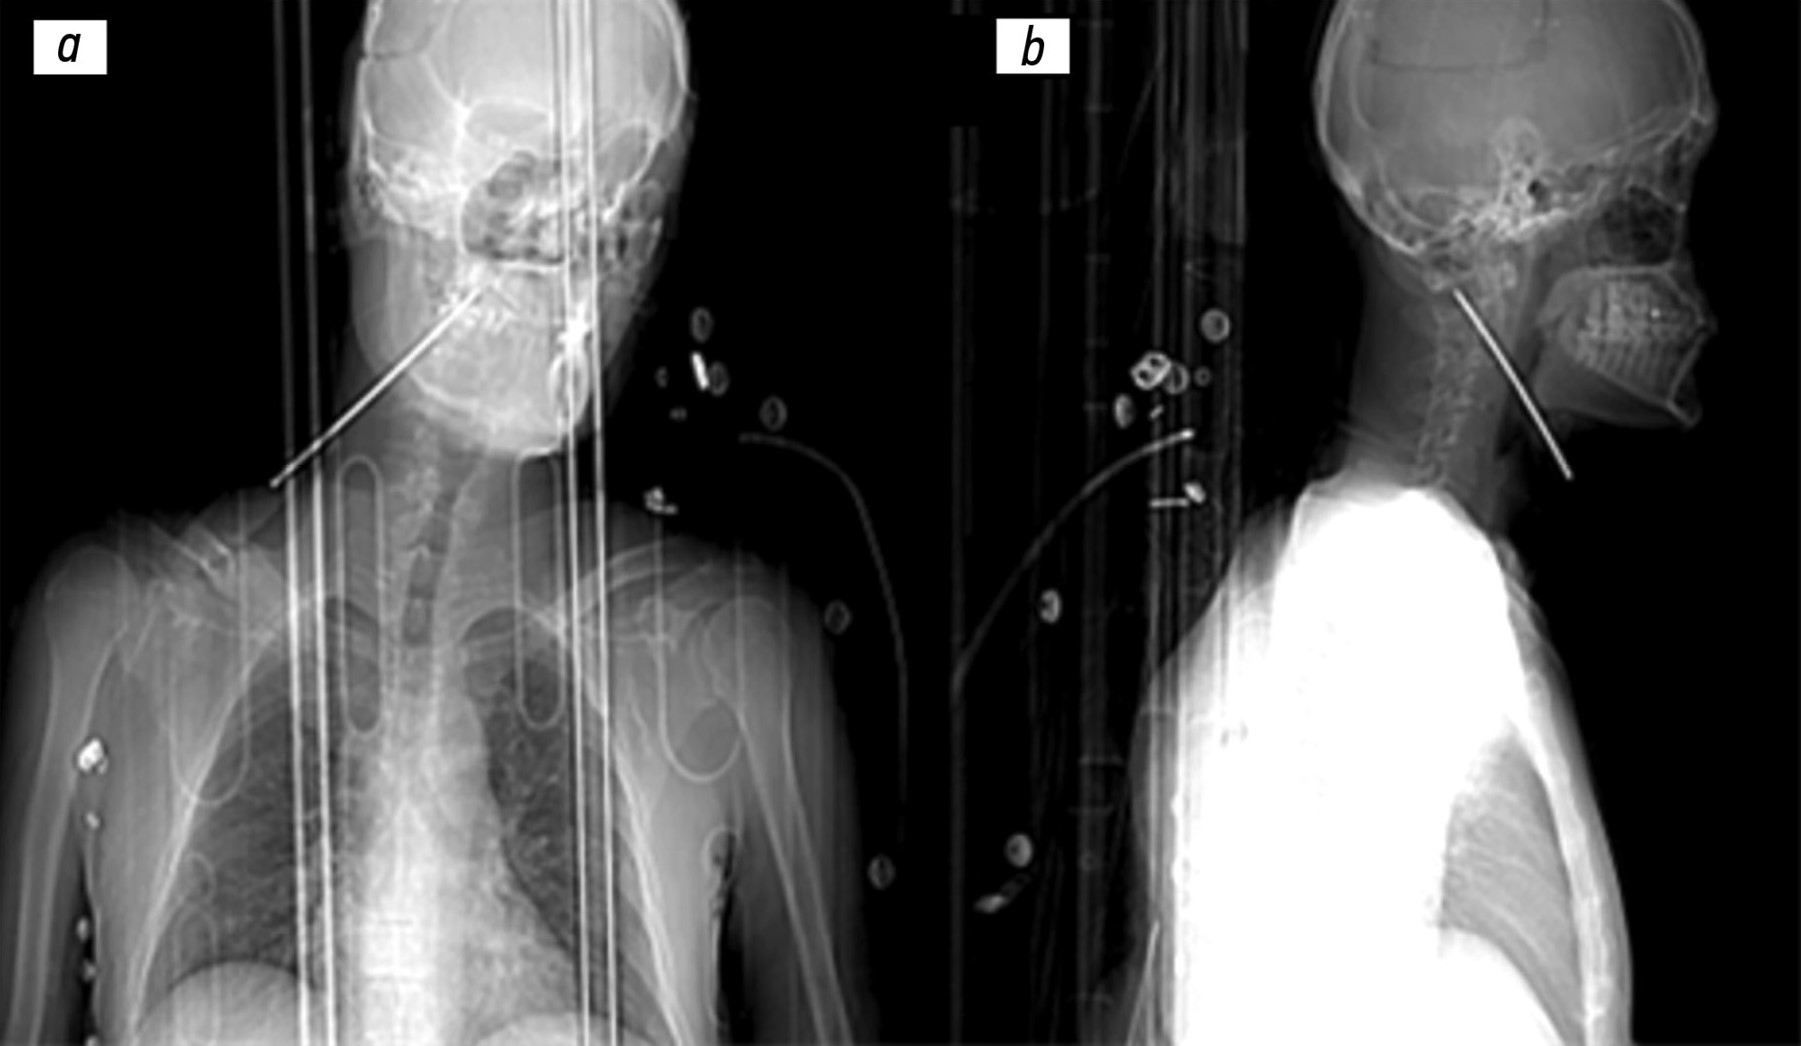

A suicide attempt with subtotal interruption of the high spinal cord without the involvement of any large vessels caused by a screwdriver in the neck: a case report

We report a case of a 40-year-old male who presented to the emergency department with a self-inflicted penetrating neck injury caused by a screwdriver, following a recent cancer diagnosis. This report outlines the urgent, radiological, and surgical management of the injury, emphasizing the challenges posed by cervical spinal trauma. Upon arrival, the patient was conscious and hemodynamically stable, despite the presence of a screwdriver lodged in the lateral cervical region. CT revealed a transfixing injury at the C2–C3 level with spinal cord disruption, without the involvement of major cervical vessels. Urgent surgical intervention, including foreign body extraction and stabilization procedures, was performed under general anesthesia. The screwdriver was removed without intraoperative complications. Despite initial stability, the patient’s condition progressively deteriorated because of respiratory failure associated with high cervical spinal cord damage. A few days later, the patient died from complications of spinal cord injury and loss of autonomous respiration. This case demonstrates the complexity of managing penetrating cervical spine trauma. Moreover, C2–C3 level injuries can rapidly lead to life-threatening neurological outcomes even in the absence of major vascular damage. Early imaging and a coordinated, multidisciplinary approach are critical for management; however, prognosis in cases of high spinal cord involvement remains poor.

639-646